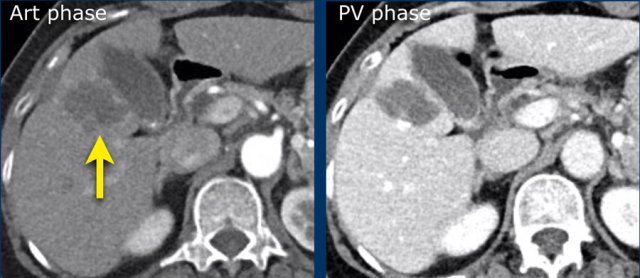

LR-5

The images show an arterially enhancing lesion with washout in segment VI. suspicious of HCC: LR-5.

Note that the arterial enhancement is faint because the patient is scanned in the early arterial phase instead of the late arterial phase in which HCC has it’s peak enhancement.

Additional small lesions can therefore be easily missed.